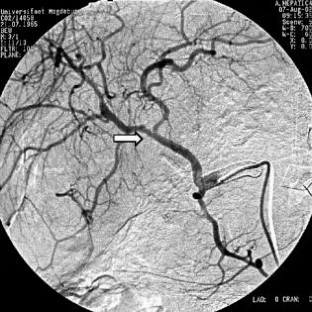

Wir berichten über das diagnostische und therapeutische Vorgehen anhand von 7 Patienten mit Blutungen aus der A. gastroduodenalis (n=5) nach pankreaschirurgischen Interventionen bei Pankreaskopfkarzinom, Rezidiv eines Liposarkoms und chronischer Pankreatitis, der A. hepatica communis (n=1) bei chronischer Pankreatitis und der A. mesenterica superior (n=1) nach akuter Pankreatitis. Anhand von 4 Kasuistiken werden unsere Erfahrungen mit der Implantation von Stentgrafts (Hemobahn®-Prothesen) vermittelt. Den Vorteil der Stentgrafts sehen wir in der sofortigen Blutstillung bei fehlendem Kontakt der Endoprothese zu infiziertem Gewebe und Erhalt der Perfusion des abhängigen Organs. Unsere positiven Erfahrungen mit diesen interventionellen Therapieverfahren erfordern jedoch weitere klinische Untersuchungen, wobei im Mittelpunkt die Indikationen, die technische Erfolgsrate, die stentbedingten Komplikationen und die Langzeitverläufe stehen sollten.

Spontaneous or postoperative hemorrhage into the abdominal cavity due to inflammatory vessel arrosion represents an uncommon but menacing situation. According to the literature, such hemorrhage is associated with a lethality of nearly 2%. Therapeutical options include reoperation and interventional radiological techniques such as endovascular catheter techniques with stent graft implantation or the embolization of vessels. We report on the management of seven cases with hemorrhage either from the gastroduodenal artery (n=5) following pancreatic surgery for pancreatic carcinoma, liposarcoma, and chronic pancreatitis or from the common hepatic artery (n=1) and the superior mesenteric artery (n=1) following chronic pancreatitis. The present article describes our experiences with stent graft implantation (hemobahn prosthesis) in four cases. Based on these experiences, we see the advantages of stent grafts in primary hemostasis without any contact to infected tissue and the preservation of regular perfusion. However, further clinical data are required focussing on indication, technical success rates, stent-related complications, and long-term outcome.